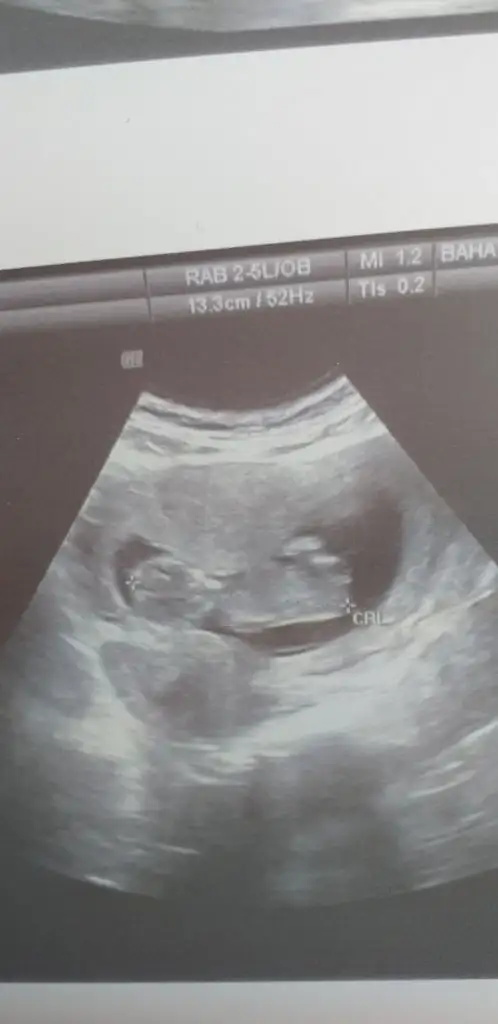

İlk usgdeki nubu tam dik degil yakınlaştırınca bozuluyor foto digerleri net değil başka varsa tahmin ederim tam dik degil paralelde değil kafa yapısınıda ekledim kızda karar verdim aslında kızda olmayada bilir

Ayyy cok merakliyim bilmiyorumİlk usgdeki nubu tam dik degil yakınlaştırınca bozuluyor foto digerleri net değil başka varsa tahmin ederim tam dik degil paralelde değil kafa yapısınıda ekledim kızda karar verdim aslında kızda olmayada bilirgenelde kafa şeklide tutmuyor

10 haftalık ama baya belli sanki

Net degil 11 yada 12 hafta olmalı nub içinBunada bakabilirsiniz kizlar